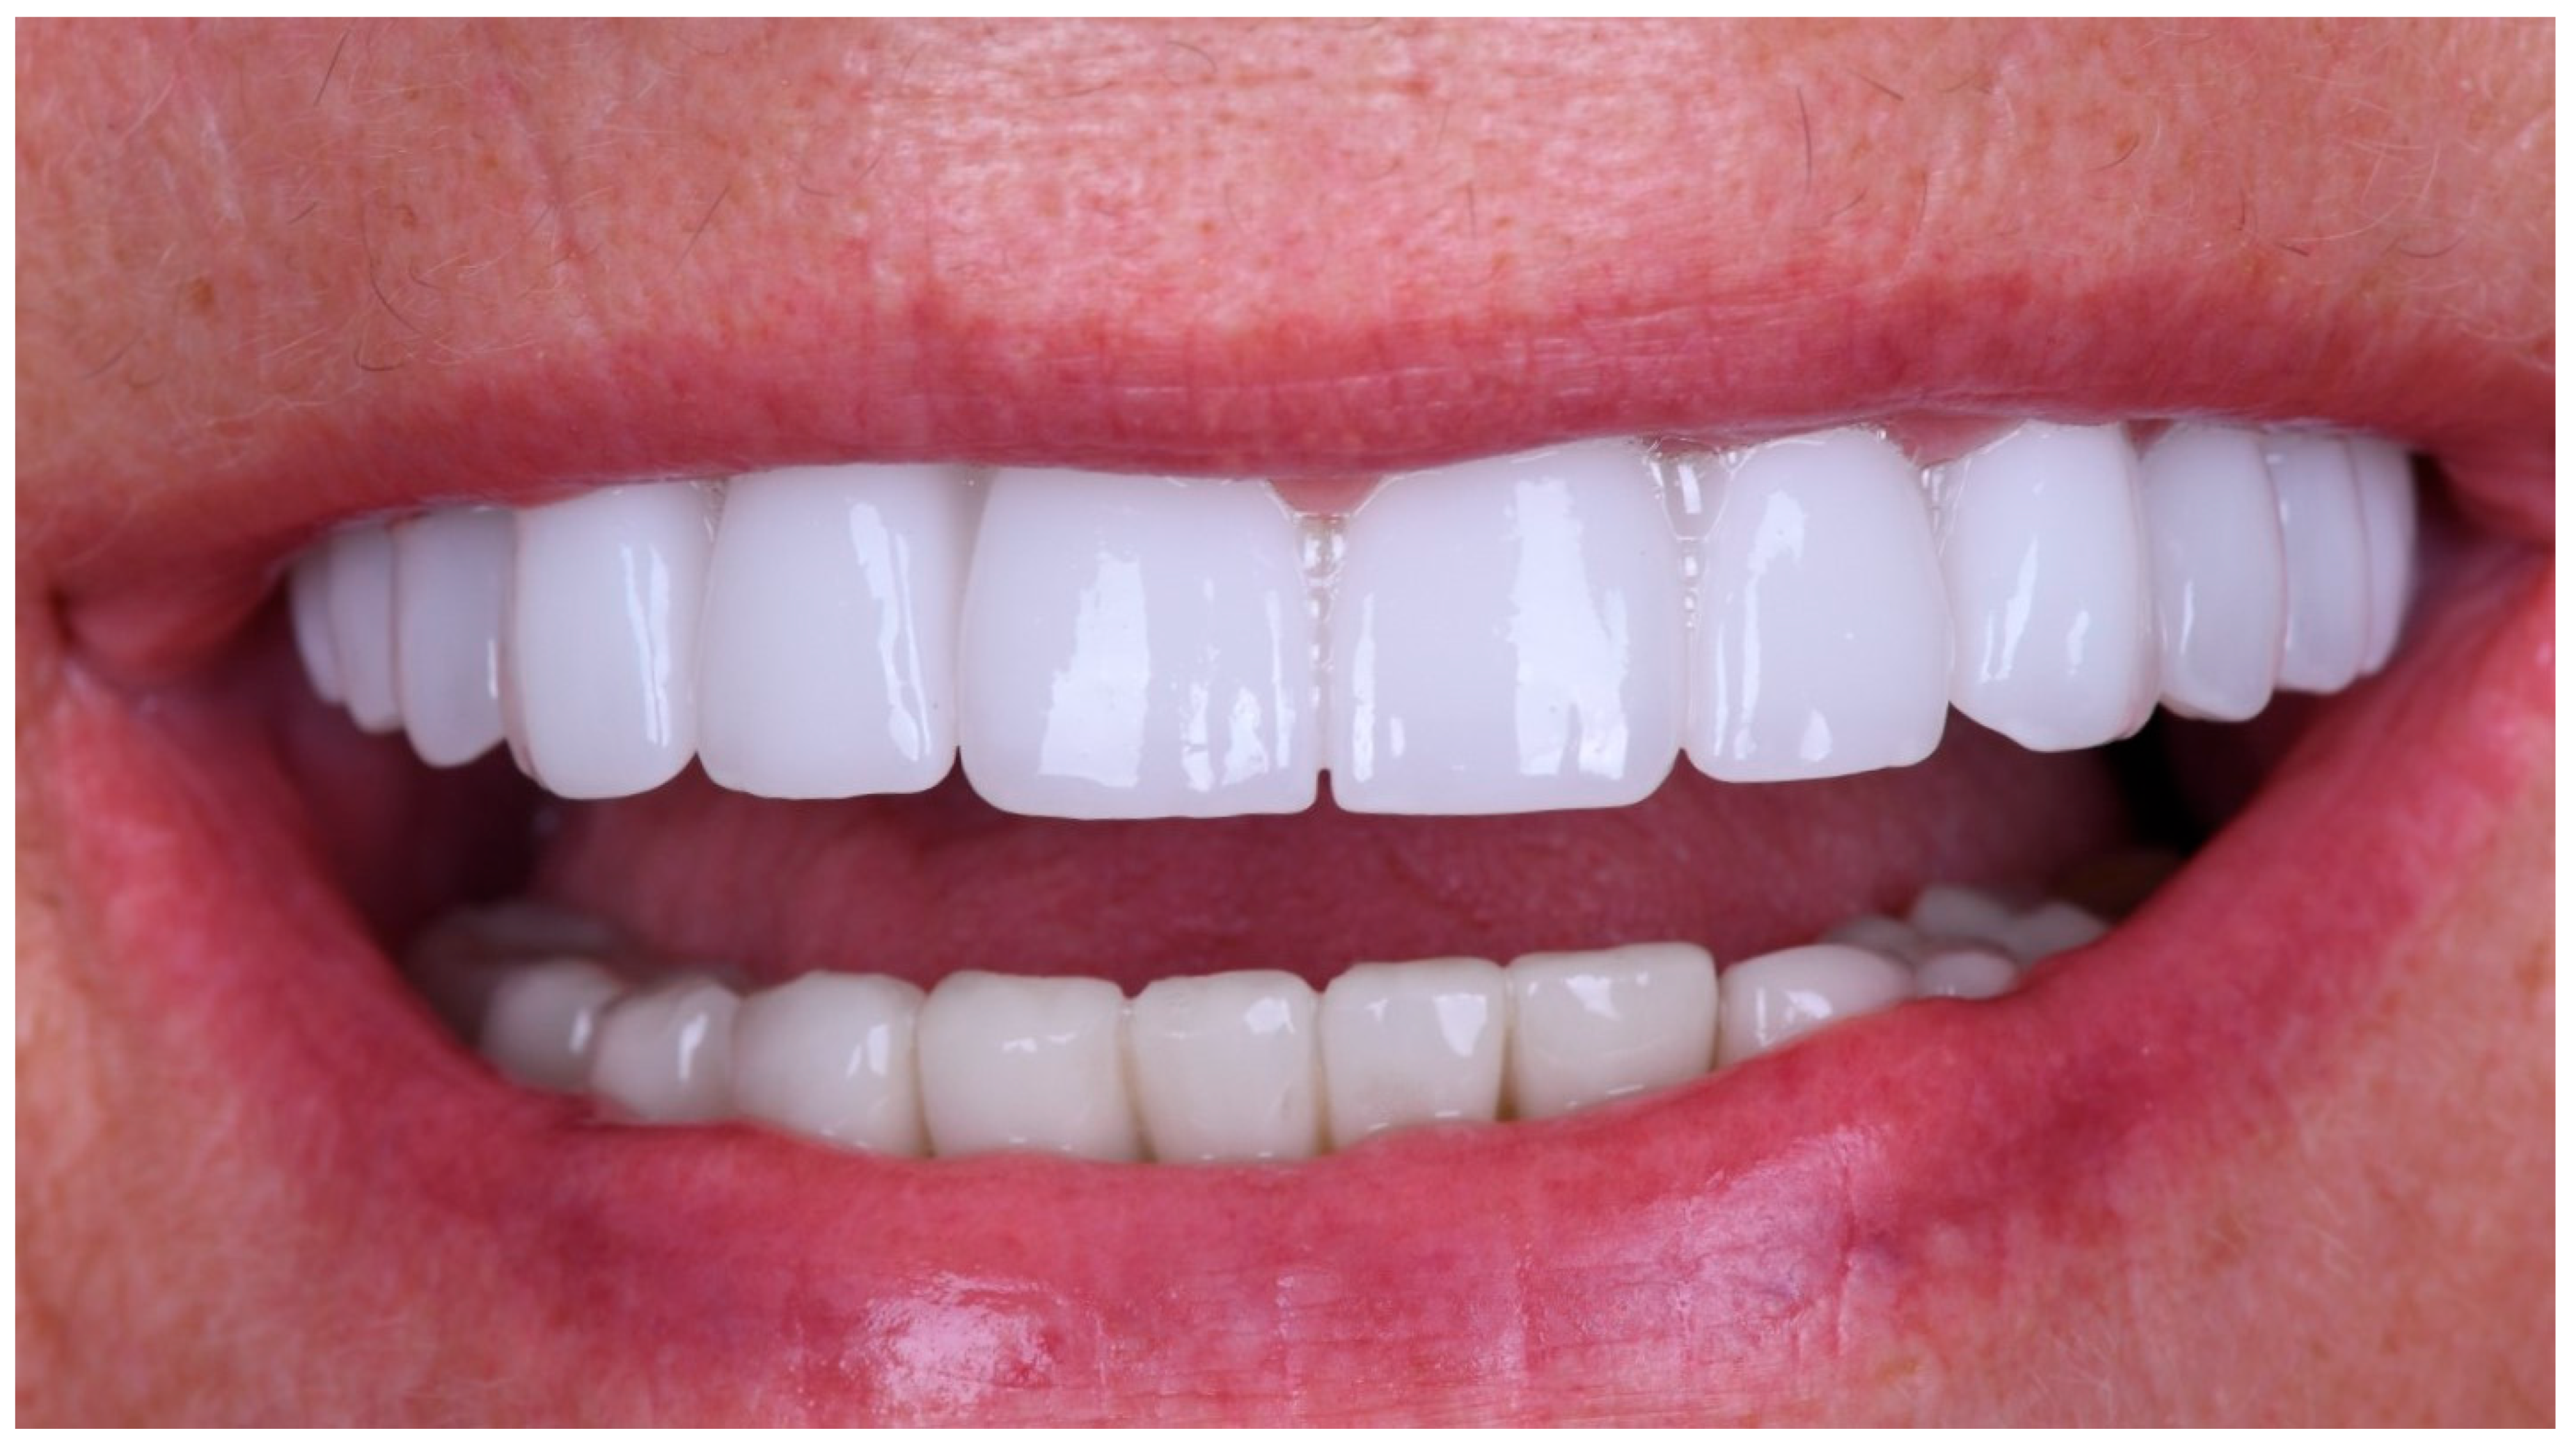

The definitive prosthesis was delivered to the patient after laboratory verification. Intraoral evaluation confirmed accurate seating, passive fit, and proper occlusal relationships. Phonetics and aesthetics were reassessed and found to be satisfactory, consistent with previous retrospective data showing high survival rates and patient satisfaction with zirconia-based full-arch prostheses [28]. A panoramic radiograph was obtained at the time of prosthesis delivery to confirm the correct seating of the framework–zirconia assembly on all supporting implants, as well as to verify stable peri-implant bone conditions.

The restoration was torqued in line with the manufacturer’s specifications, and the screw access channels were sealed with composite resin. The definitive clinical situation in the patient’s mouth is shown in Figure 18 and Figure 19.

Static and dynamic occlusion were subsequently assessed using a digital OccluSense pressure analysis system (Bausch, Hainspitz, Germany).A follow-up was scheduled after 4 months, and the prosthesis demonstrated stable function and satisfactory aesthetics. The patient was fully satisfied.

At the 4-month follow-up, peri-implant tissues were clinically healthy, with no signs of inflammation or suppuration. Clinical and routine radiographic assessment performed during follow-up revealed no pathological findings. The patient reported high satisfaction with function and aesthetics. No biological, mechanical, or technical complications were observed during the follow-up period. The patient was also seen at a later recall visit, during which stable function and satisfactory aesthetics were maintained.

Figure 18. Extraoral frontal view of the definitive full-arch prosthesis in situ, demonstrating the final aesthetic outcome.

Figure 19. Extraoral smile view of the patient with the definitive restoration in situ.